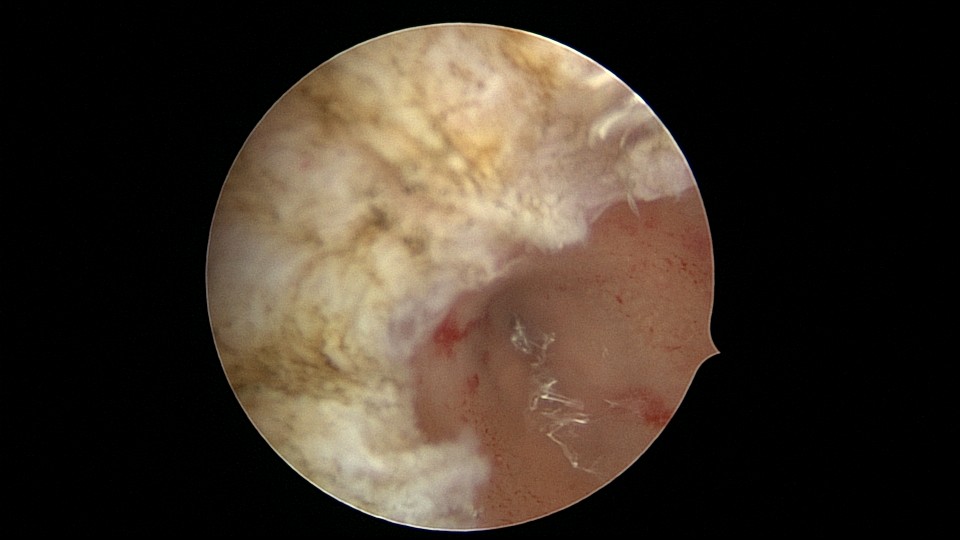

患者33岁,G5P2,顺产2次,胎停清宫后月经量减少,外院B超提示宫腔粘连。2021年5月宫腔镜探查,宫腔重度粘连,宫腔狭小,右侧输卵管开口可见,左侧输卵管开口未见,单极电针分粘,恢复宫腔形态,显露左侧输卵管开口(僵硬)。2021年6月宫腔镜二探取球囊,宫腔形态正常,双侧输卵管开口可见,宫内膜薄。2022年7月自然妊娠,2023年3月孕39+周顺产分娩。现38岁,G6P3,顺产3次。